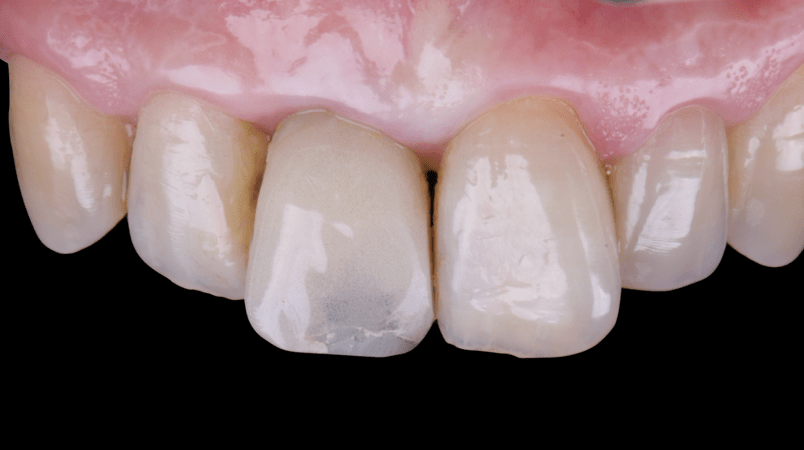

On the same day as the surgery, an immediate-load provisional crown was delivered. This restoration was fabricated in acrylic resin and screw-retained on the implant, following the “one abutment one time” principle. The provisional crown was carefully adjusted to avoid occlusal loading while supporting the peri-implant soft tissue architecture during the healing phase.

The provisional not only satisfied the patient’s functional and esthetic demands but also played a key role in shaping the emergence profile and conditioning the gingival margin. By providing a provisional solution immediately, the patient was able to leave the clinic with a natural-looking smile, avoiding any psychological or social impact associated with tooth loss in the anterior maxilla.

After an appropriate healing period, the definitive prosthesis was planned and delivered. A screw-retained zirconia crown was fabricated to ensure long-term durability, optimal esthetics, and retrievability. Zirconia was selected for its mechanical strength and excellent esthetic properties, blending seamlessly with the adjacent natural dentition in both form and color.